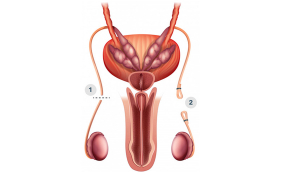

Вазектомія.Чоловіча стерилізація у Івано-Франківську

Турбота про запобігання небажаній вагітності у нашій країні вважається суто жіночою проблемою. За даними статистики, у 75% подружніх пар про контрацепцію дбає жінка. Тим часом у європейських країнах і США чоловіча контрацепція популярна серед подружніх пар. Зокрема, вазектомія третя з методів запобігання після протизаплідних таблеток для жінок і використанням презервативів.